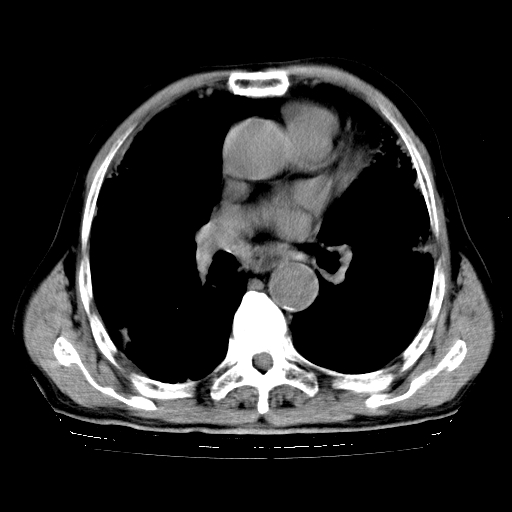

标题: CT25149:男,69岁,反复咳嗽、咳痰五年余,呼吸困难三天。 [打印本页]

男,69岁,反复咳嗽、咳痰五年余,呼吸困难三天。

慢支伴感染、肺气肿、肺心病

慢支伴感染、肺气肿、肺心病。双肺间质性改变(间质纤维化)。